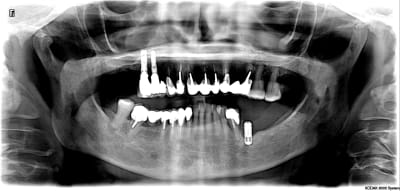

Je viens de récupérer un cas de prothèse sur implant d’un confrère. 14 15 jumelées avec 13 en extension. Le tout s’est dévissé. Je dois déposer et refaire….

et voila messieurs !

Ce sont des Serf... je bosse sur mac et c'est pas évident quand on ne maitrise pas mac pour sortir les radios. J'espère que ça conviendra

serf EVL donc connexion à plat...ce qui veut dire multiunits inutiles si tu n'utilises pas l'hexagone (ce qui est le cas déjà ici si tu étudies bien la rétroalvéolaire)

mais!: l'implant le plus mésial n'est pas dans un axe idéal ce qui veut dire que l'émergence de la vis sera merdique à gérer si tu veux faire de la transvissée...

tu n'as pas d'autre choix que de refaire de la scellée pour ce cas...et petit conseil, utilise des piliers indexés et non pas des piliers sans indexation comme ici...

amha çà c'est dévissé car les piliers n'ont pas étés mis dans la bonne position, ils ont été vissés/serrés de travers...la mastication les a fait revenir dans la bonne position...mais du coup ils ne sont plus serrés...

P.S: le vieil IMZ est bon pour le haricot...

PS: En 35-34 c'est l'exemple même de ce qui arrive dans un os D1. Certains appeleraient ça une peri implantite. .. à tort à mon avis. Il faut rétablir la vascularisation sinon re échec 🤔😕

C'est évident à la vue de ta pano. repenses au plan de traitement.